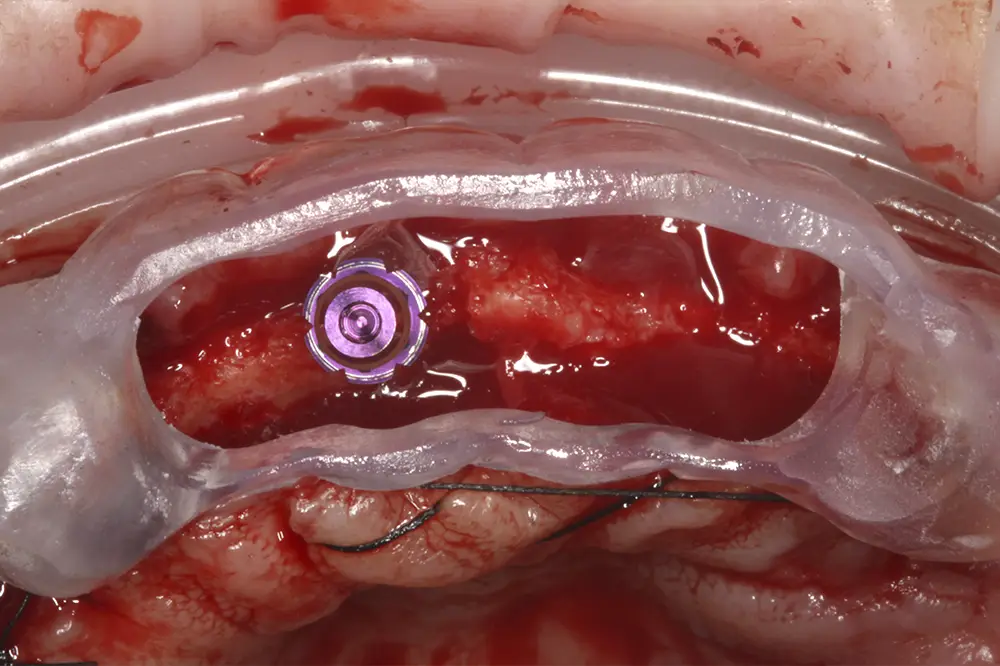

Una vez realizada la planificación de forma exhaustiva, y analizadas las técnicas quirúrgicas e implantes que se van a emplear en cada zona del maxilar superior, se procede a la cirugía de implantes. Para realizar una inserción de los mismos guiada a través de la prótesis, se confecciona una guía quirúrgica que nos sirve de referencia durante la cirugía, que se posicionará en los caninos superiores que se deciden mantener para la fase de provisionalización del paciente (figs. 19-22). Tal como se ha explicado, podemos observar en las imágenes de la cirugía la sobrecorrección que se lleva a cabo de las zonas con mayor atrofia a nivel horizontal (figs. 23-24). Tras la cirugía, los implantes se dejan en dos fases quirúrgicas, debido al empleo de técnicas accesorias y se coloca un provisional sobre los dos caninos que se conservan temporalmente (figs. 25-26). Estos caninos que se conservan se tratan mediante tratamiento periodontal quirúrgico para una mejor cicatrización postoperatoria y alargar la vida de los mismos el tiempo que se necesita para los provisionales.

Figs. 19-22. Colocación de los implantes posicionándose tridimensionalmente a través de la guía quirúrgica.